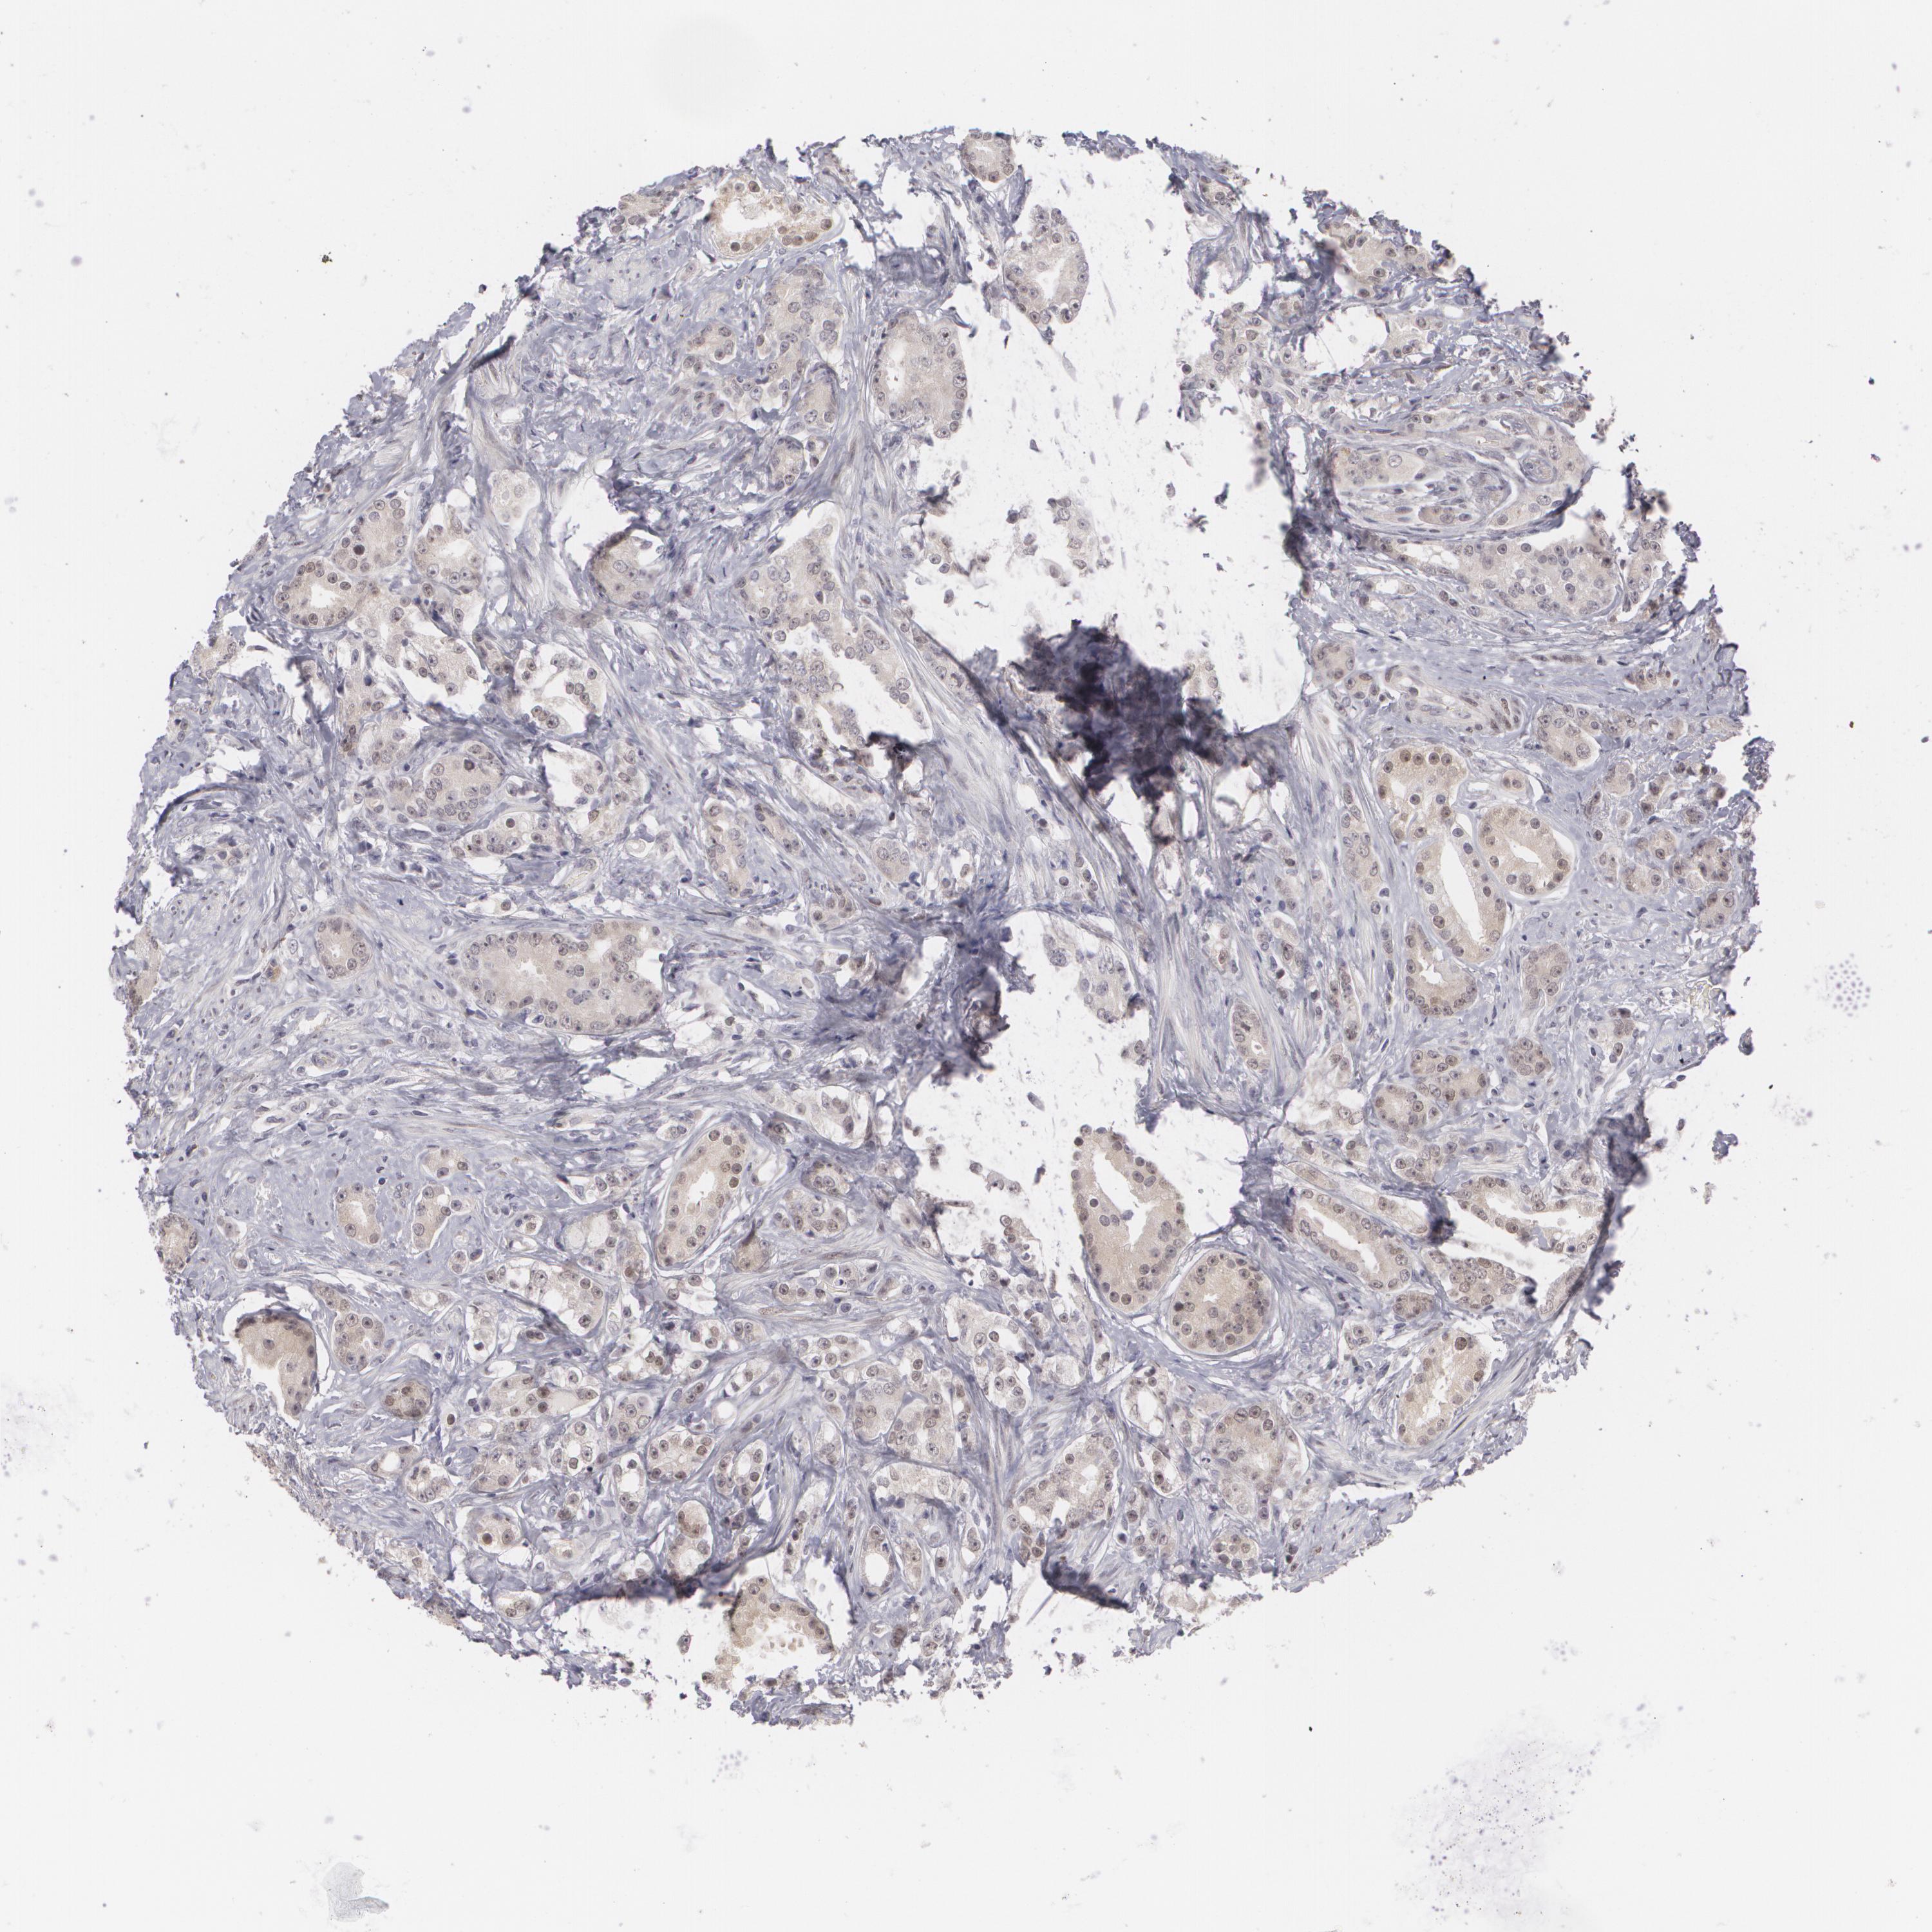

PROSTATE CANCER - Protein expressioni

A mouse-over function shows sample information and annotation data. Click on an image to view it in a full screen mode. Samples can be filtered based on level of antibody staining by selecting one or several of the following categories: high, medium, low and not detected. The assay and annotation is described here.

Note that samples used for immunohistochemistry by the Human Protein Atlas do not correspond to samples in the TCGA dataset.

Antibody stainingi

Antibody staining in the annotated cell types in the current human tissue is reported as not detected, low, medium, or high, based on conventional immunohistochemistry profiling in selected tissues. This score is based on the combination of the staining intensity and fraction of stained cells.

Each image is clickable and will lead to virtual microscopy that enables deeper exploration of all samples and also displays staining intensity scores, fraction scores and subcellular localization as well as patient and tissue information for each sample.

Antibody HPA001499

Antibody CAB004540

Staining

High

Medium

Low

Not detected

Intensity

Strong

Moderate

Weak

Negative

Quantity

>75%

75%-25%

<25%

None

Location

Nuclear

Cytoplasmic/membranous

Cytoplasmic/membranous,nuclear

Adenocarcinoma, Medium grade

Adenocarcinoma, High grade

Adenocarcinoma, Low grade